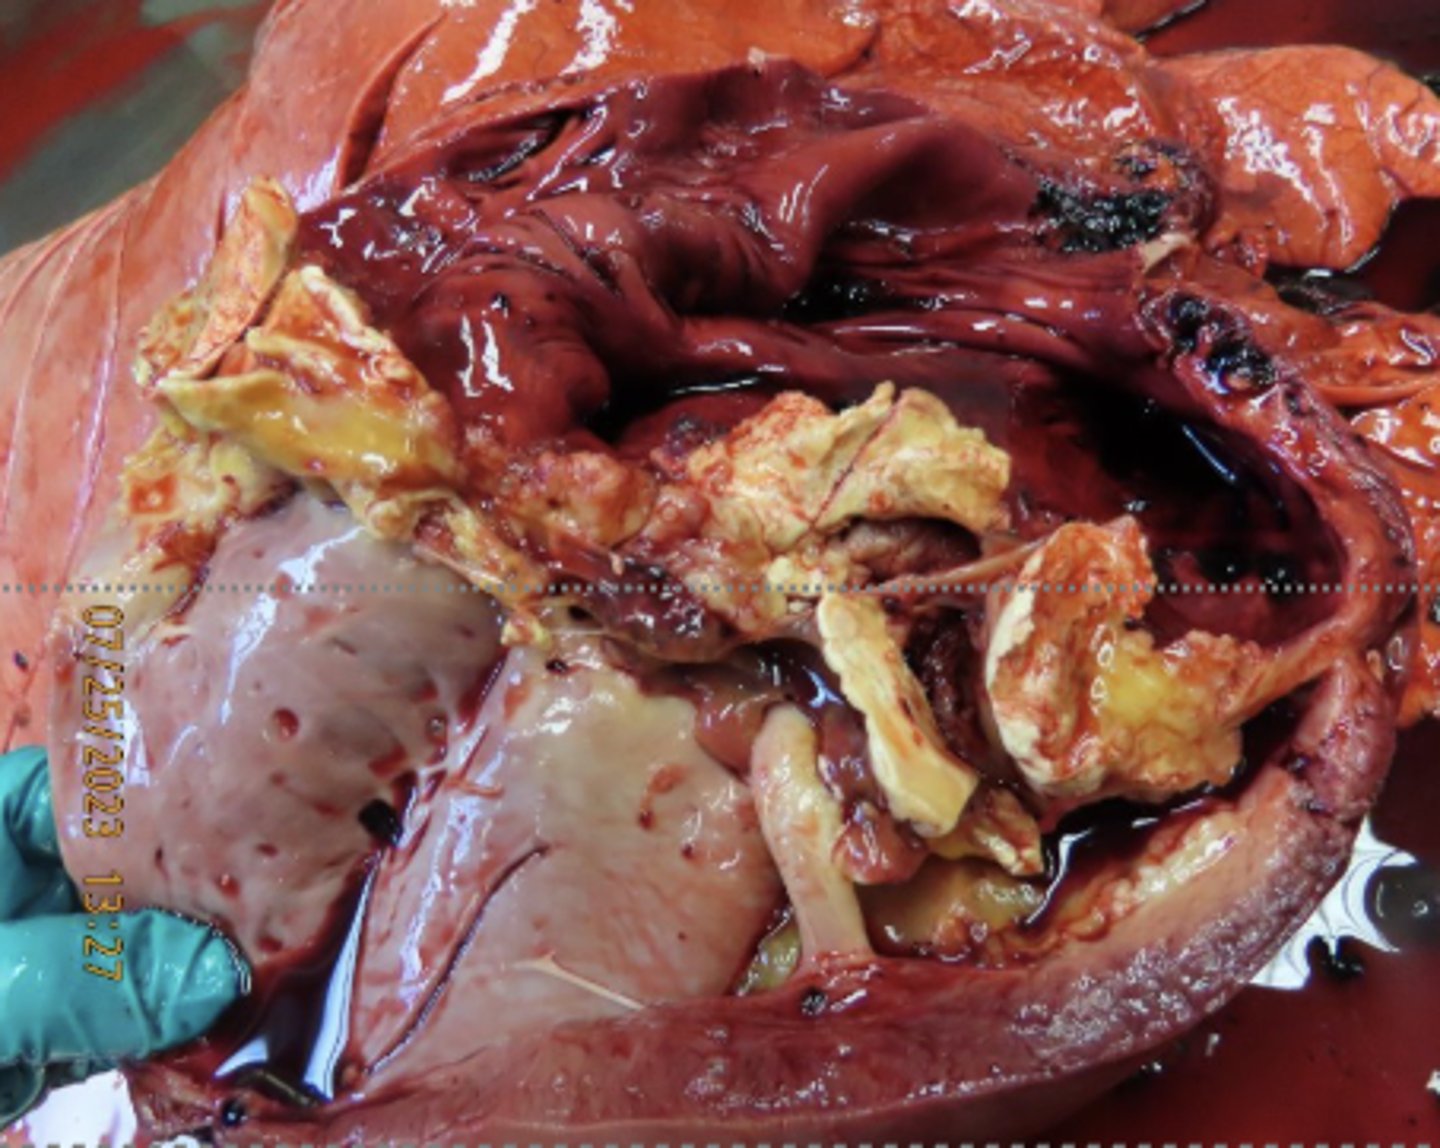

Flukes!!

-migration of flukes through liver parenchyma

What caused this lesion in the liver of a deer?

Fascioloides magna migration

-black lines

-hepatocytes have filled with fat (white spots) due to hypoxia

-fibrous connective tissue from damage

What has caused this gross appearance of this liver?